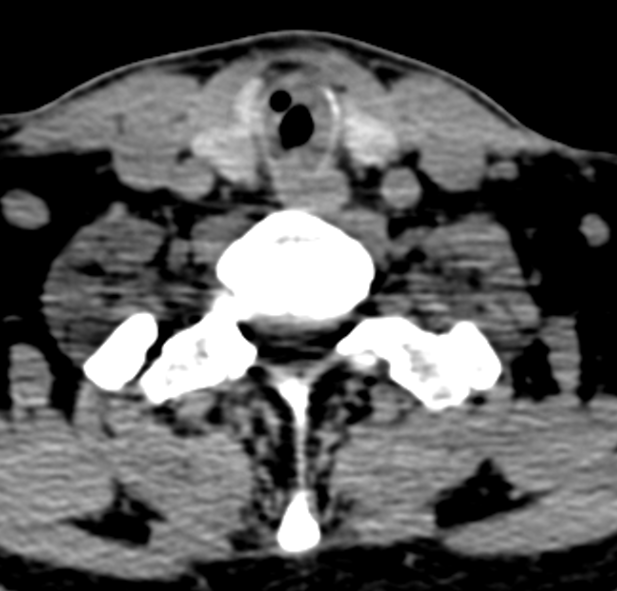

“这相当于患者每分每秒都在通过一根饮料吸管呼吸。”CT显示,狭窄处管腔4mm,狭窄程度高达80%,狭窄段长达2厘米。广州市花都区人民医院呼吸与危重症医学科主任医师招树涛表示,一旦有少量痰液堵塞,就可能引发致命性窒息,抢救窗口期极短。